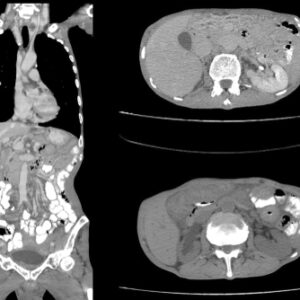

顯影劑(Contrast Media 或 Contrast Agents),又常被稱為造影劑,是一種在進行醫學影像檢查時引入體內的特殊物質。它的主要用途是改變人體內部特定器官、血管或組織的對比度,使這些部位在 X 光、電腦斷層掃描(CT)或磁力共振掃描(MRI)的影像中顯得更為突出和清晰。透過注射或口服顯影劑,醫生能夠更準確地觀察器官的結構及血流情況,從而精準辨識微小腫瘤、血管阻塞、發炎或組織異常。

坊間常有一個迷思,認為所有高階醫學影像檢查都必須使用顯影劑。事實上,並非所有CT或MRI都必須打顯影劑。許多基礎的檢查(例如骨骼結構掃描、部分關節損傷檢查、或是初步的腦部出血篩查)在不注射顯影劑(平掃,Plain Scan)的情況下已經能提供足夠的診斷資訊。是否需要使用顯影劑,完全視乎主診醫生根據患者的具體病歷、疑似疾病的種類以及檢查的目的來作出的專業判斷。